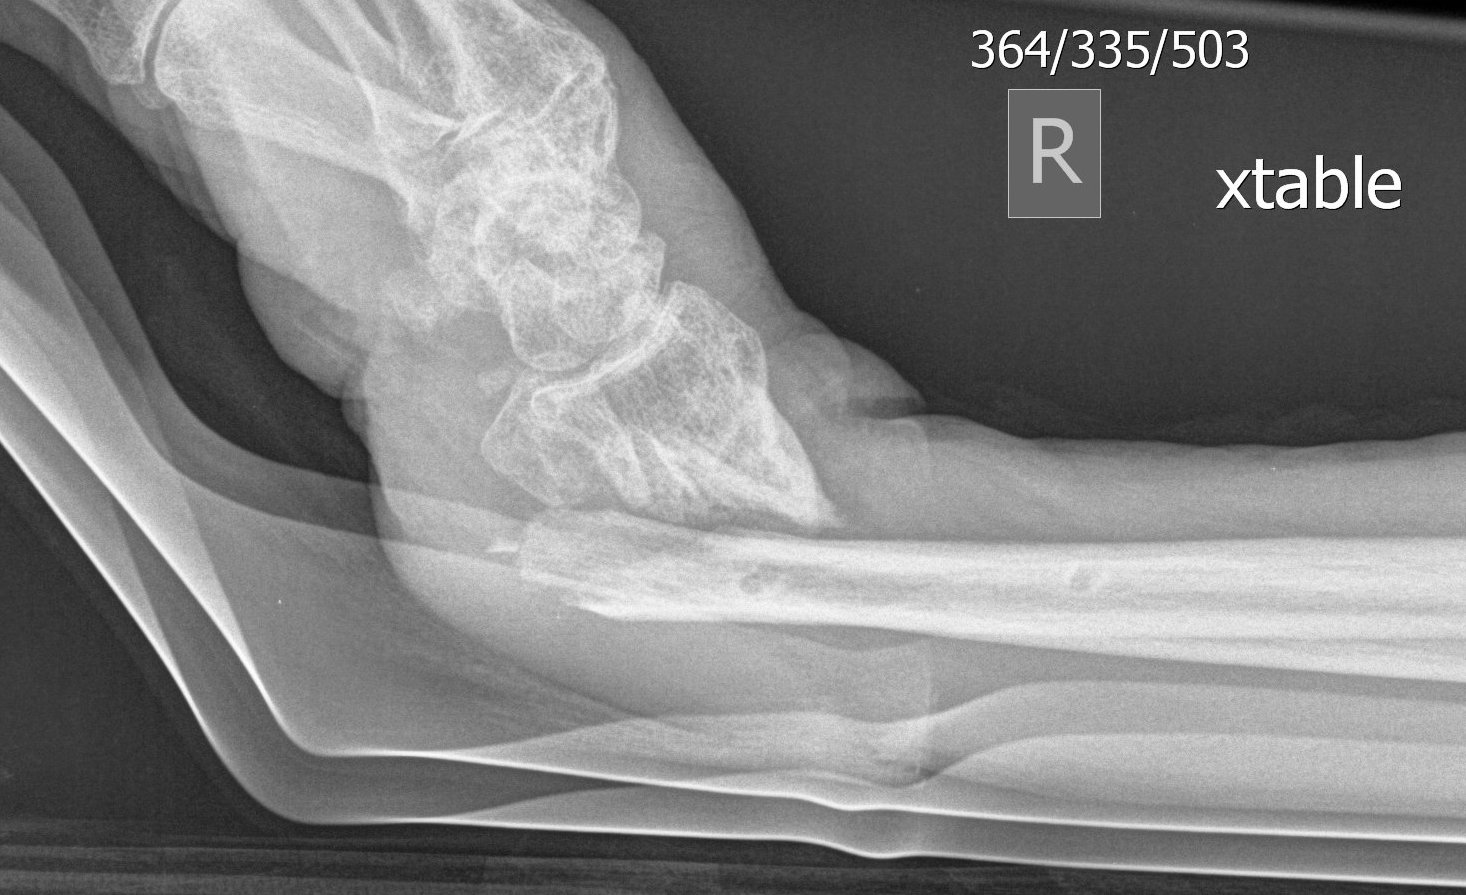

DRDR

Dr shortDR short

Distal radius fracture with shortening and dorsal tilt